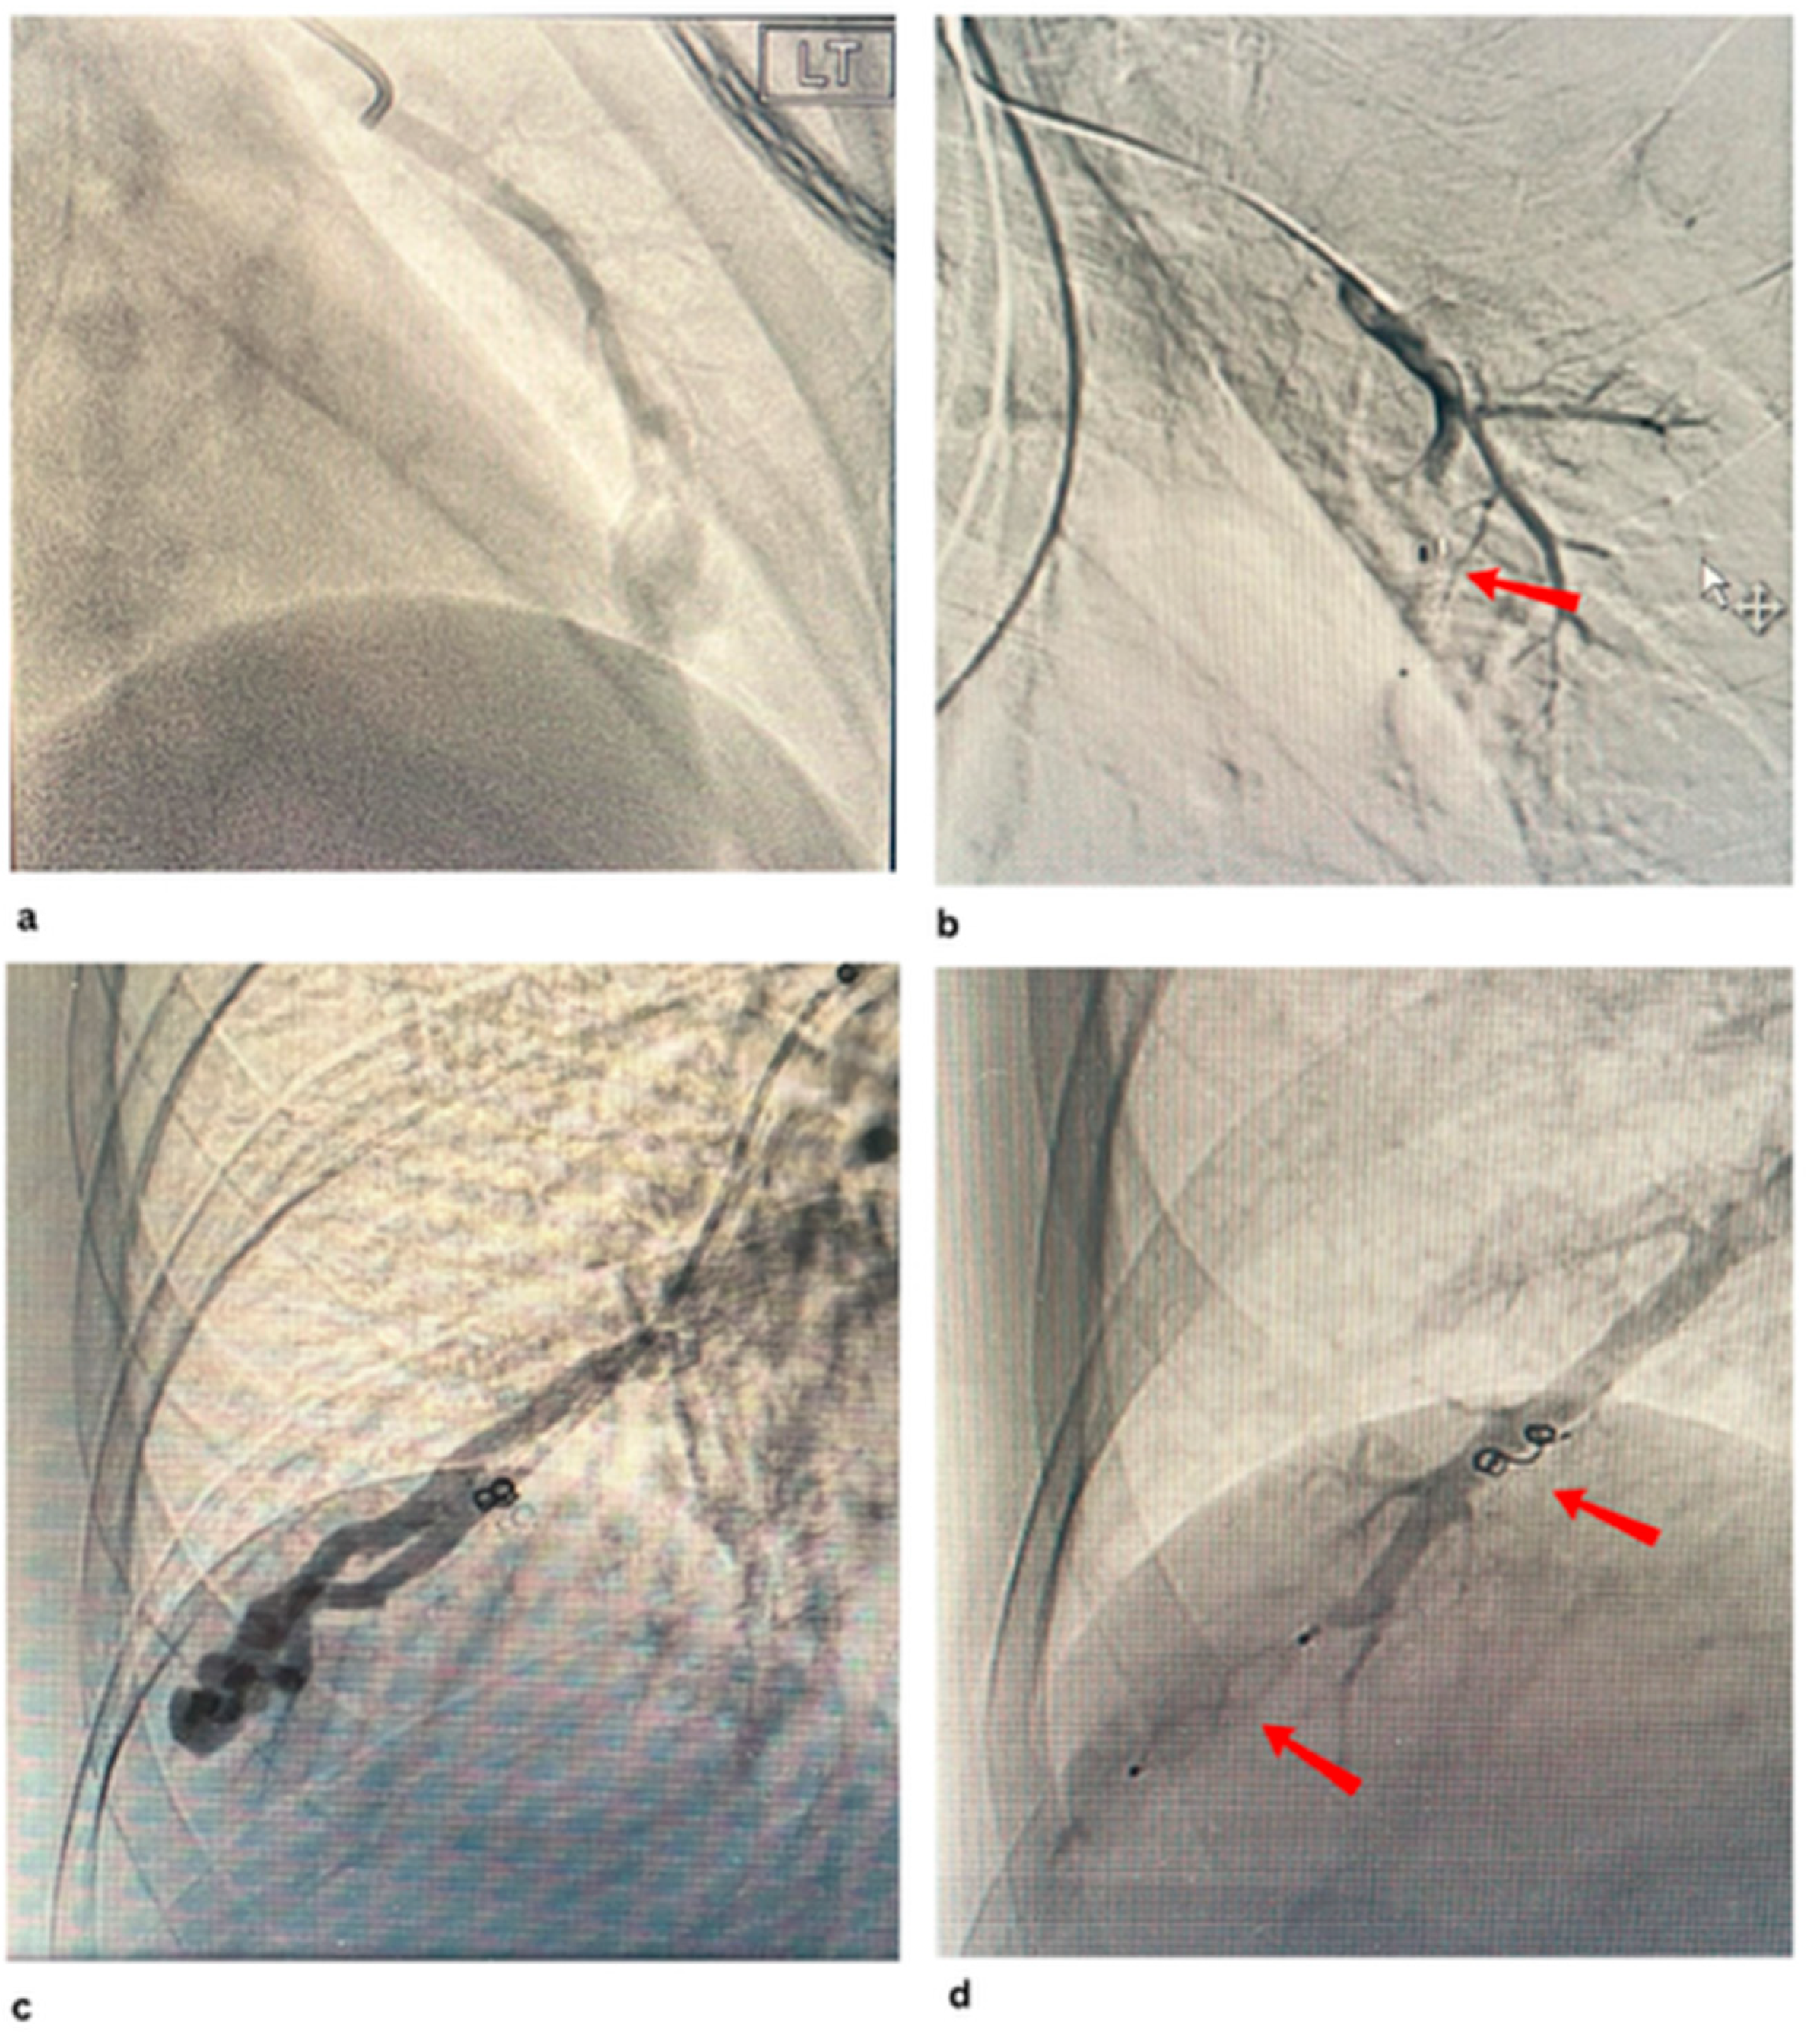

- Hayashi, S.; Baba, Y.; Senokuchi, T.; Nakajo, M. Efficacy of Venous Sac Embolization for Pulmonary Arteriovenous Malformations: Comparison with Feeding Artery Embolization. J. Vasc. Interv. Radiol. 2012, 23, 1566–1577. [Google Scholar] [CrossRef]

- Srinivas, S.; Roberts, D.G.; McWilliams, J.P.; Cusumano, L.R. Feeding-Artery Microvascular Plug Embolization Versus Nidus-Plus-Feeding-Artery Coil Embolization of Pulmonary Arteriovenous Malformations. J. Clin. Med. 2025, 14, 2980. [Google Scholar] [CrossRef]